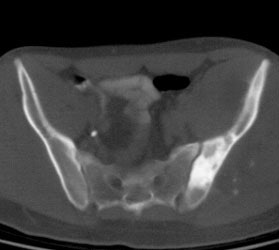

Ewings sarcoma of the pelvis: The bone scan demonstrates extensive, intense tracer uptake involving the left iliac wing, extending into the ischium and left sacrum. CT scan revealed a mixed, but predominantly sclerotic lesion involving the bone with an associated soft tissue mass. Note that the sacrum fails to demonstrate a CT abnormality. The T2 weighted images from the patients MR exam more clearly defines the lesion. Sacral involvement is clearly evident (white arrows) and there is also a large soft tissue component. |